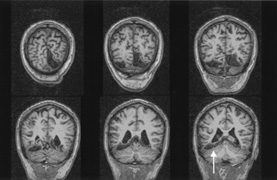

DISORDERS OF COLOR PROCESSING Cerebral Dyschromatopsia Cerebral (central) achromatopsia refers to complete loss of color perception, whereas cerebral dyschromatopsia indicates some residual color perception, as is most often the case. Both are rare. Hemiachromatopsia refers to color loss restricted to the contralateral hemifield,234,235 and may be more common but under-recognized. Achromatopsic patients generally are symptomatic, complaining that the world appears in shades of gray.236–239 Some also report that the world appears less bright240 or has a “dirty gray” tinge.241 Less frequently, patients report a tinge to the world, as if peering through a colored filter.242 Daily activities that use color discrimination are impaired, such as distinguishing coins, stamps, or traffic lights: A good account exists of the experience of an achromatopsic artist.243 Effects on “color constancy” are an important issue. The wavelengths reaching the eye from an object depend on both its reflectant properties and the light illuminating the scene. Yet, the color of objects remains stable under a wide range of environmental and lighting conditions.244,245 For instance, an apple continues to look red in sunlight, incandescent light, and fluorescent light, in an orchard or a grocery display. This ability to “discount the illuminant” depends on neural computations in retina and cortex.244 These computations likely average the spectral luminance over large regions of the surrounding background to deduce the nature of the illuminant, and this information is then taken into account to derive the true color of any object in the scene.244,246 A defect in color constancy should result in color percepts that vary with changes in illumination. Patients with achromatopsia have a more severe deficit, in that they lack any color percept at all. Testing such patients for constancy of something they do not perceive is paradoxical, but this can be done on dyschromatopsic patients, who have some residual hue sensitivity. Some studies have shown that color constancy is impaired in these patients.247–250 These patients all had bilateral lingual and fusiform gyral lesions, except for one unilateral case.248 Not all color perception is lost in achromatopsia. Some color input from the cones and retinal ganglion cells of the parvocellular pathway still can be processed. Thus, both trichromacy and color opponency have been shown in photopic spectral sensitivity curves247,251,252 and evoked potential or psychophysical measures of chromatic contrast sensitivity.252,253 Likewise, performance with anomaloscope testing can resemble an anomalous trichromat rather than a monochromat, despite the experience of the world as monochromatic “shades of gray.”254 Achromatopsics can use color-opponent signals to locate chromatic boundaries, even though they cannot perceive the colors that determine those boundaries. Thus achromatopsics can detect the movement of chromatic stimuli,255,256 even performing at normal levels with suprathreshold chromatic contrast.257 This indicates that wavelength variation is still perceived, even if color is not. Achromatopsia is seldom an isolated finding. Most commonly it forms one component of a tetrad that includes superior quadrantanopia, prosopagnosia, and topographagnosia. Superior field loss is almost always present, because the ventral occipito-temporal lesion that causes achromatopsia frequently extends into the inferior calcarine cortex or optic radiation. Similarly, only a few cases without prosopagnosia have been reported.258 Experimental testing has revealed in some patients a problem with detecting stimuli with low salience,259 which has also been described in monkeys with V4 lesions, and thought to indicate inefficient attentional allocation in form processing. Other occasionally associated defects include visual object agnosia,251,260 alexia in achromatopsic patients with right hemianopia,238,258 and amnesia with additional ventral temporal lobe damage.238,260 Achromatopsia is caused by lesions of the lingual and fusiform gyri,245,261 as confirmed by modern imaging.240,241,251,254,258,262 Lesions of the middle third of the lingual gyrus or white matter behind the posterior tip of the lateral ventricle may be critical.240,263 Bilateral lesions are necessary for complete achromatopsia. In monkeys, color-selective responses are found in area V4.245 However, lesions of V4 do not impair hue perception significantly.264–269 Rather, defects in chromatic perception require extensive bilateral lesions, including areas TE and TEO.270,271 In humans, functional imaging reveals several areas involved in color processing, notably a V4 homologue and a second area named V4 alpha or V8 in the fusiform gyrus,272,273 as well as other more distant regions.274–276 Thus color processing involves a network of regions, and it is probable that a severe achromatopsic defect may require damage to or disconnection of several components of the network, rather than just a lesion of a single region like the human V4 homologue.267,277,278 Achromatopsia is most often caused by strokes. Bilateral sequential or simultaneous infarctions in the territories of both posterior cerebral arteries can occur, or multiple infarcts may result from a coagulopathy.279 Achromatopsia may be the first symptom of a stroke or the outcome of an initial cortical blindness. Other bilateral lesions causing achromatopsia include herpes simplex encephalitis,251 cerebral metastases,258 repeated focal seizures,280 focal dementia,281 and even migraine aura, causing a transient achromatopsia.282 Temporo-occipital white matter damage has caused a reversible dyschromatopsia in one patient with carbon monoxide poisoning,283 a condition that usually causes an apperceptive agnosia with spared color perception.245 HEMIACHROMATOPSIA. Achromatopsia in the contralateral hemifield alone can follow unilateral right or left occipital lesions (Fig. 18). Patients are typically asymptomatic until the defect is demonstrated on examination.234,235 Hemiachromatopsia is usually associated with a superior quadrantanopia;234,235,241 therefore, the color defect is only demonstrable in the remaining inferior quadrant. The preserved color vision in the ipsilateral hemifield allows normal or near-normal performance on centrally viewed tests of color vision such as pseudoisochromatic plates. The incidence of hemiachromatopsia is probably underestimated, given its asymptomatic nature and the failure of routine clinical color tests to detect its presence.